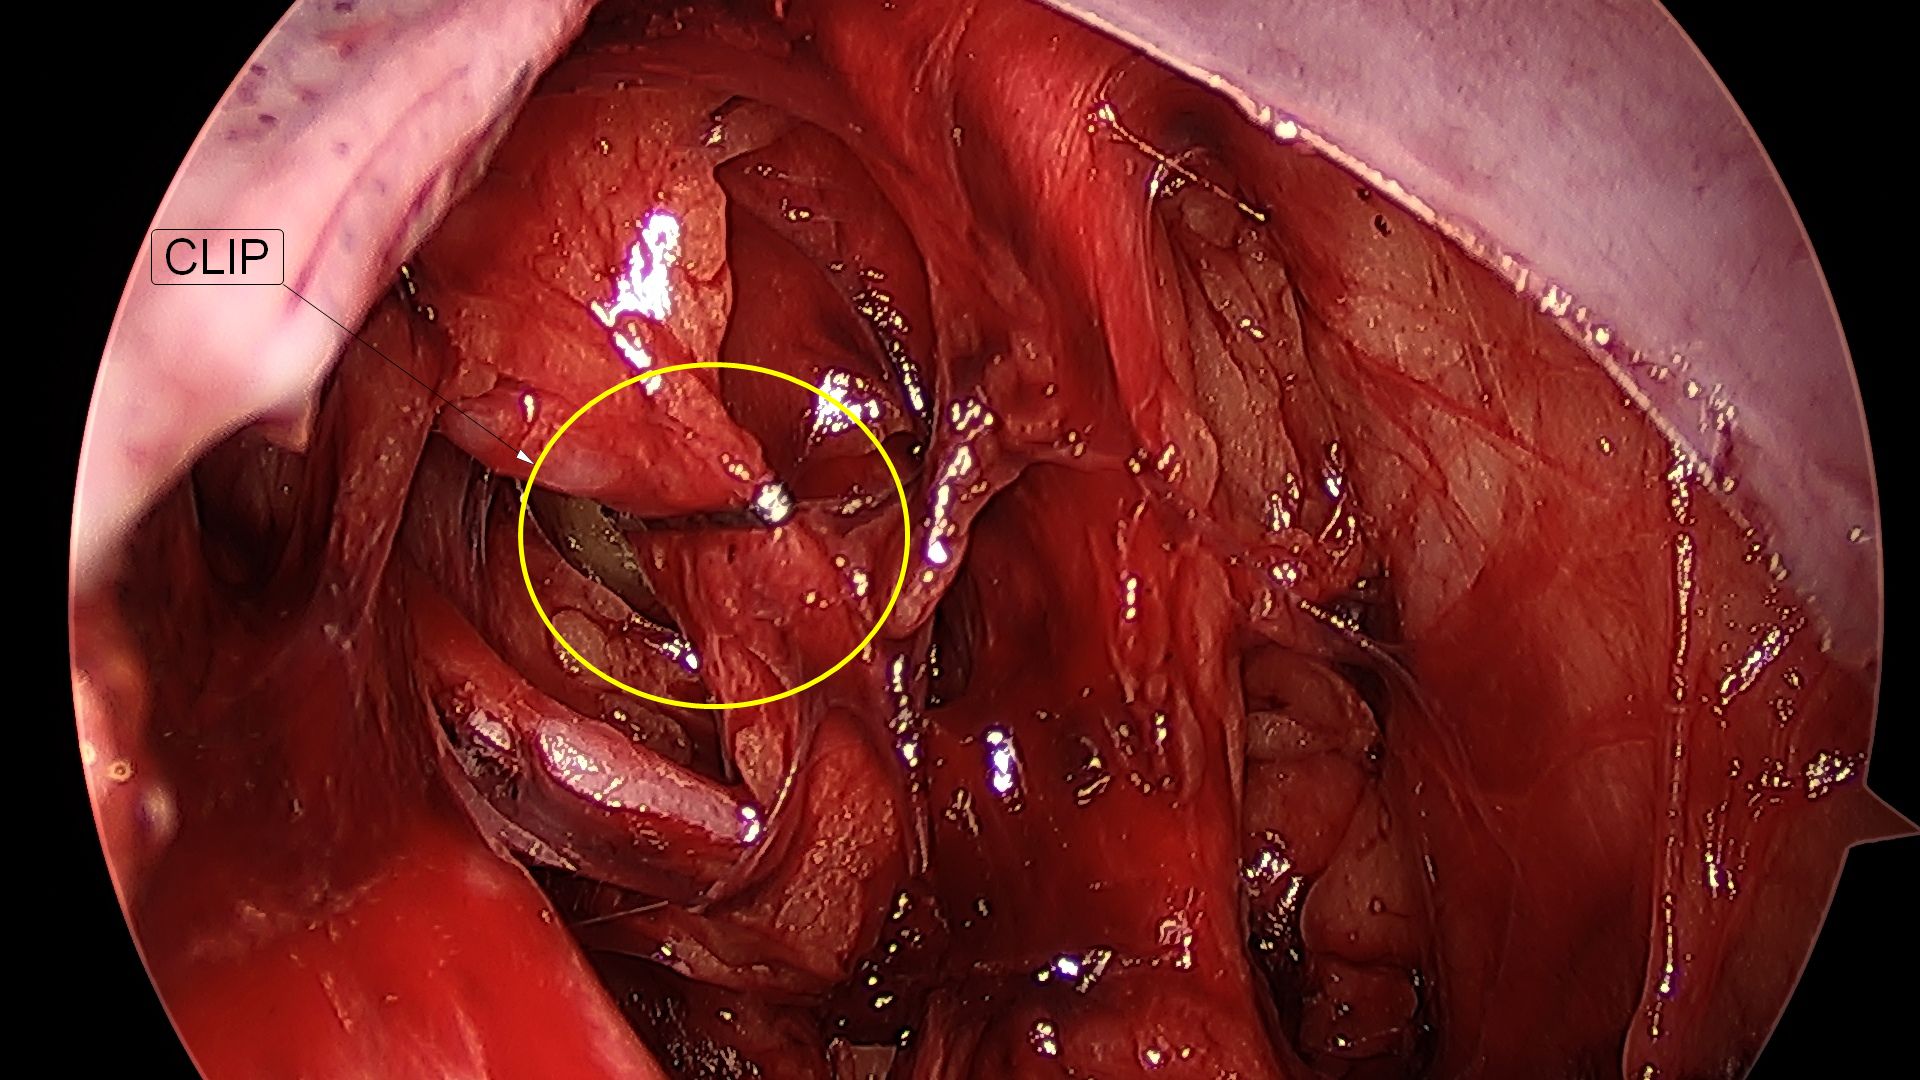

A fecundação do óvulo ocorre na trompa e a partir de então, com os movimentos peristálticos, esse óvulo fecundado é direcionado para o útero, Na gravidez tubária, notamos uma falha nesses movimentos, fazendo com que a gestação se desenvolva no interior da trompa. Com o avançar da gravidez, ocorre a dilatação da trompa, acompanhada de dor importante na parte baixa do abdômen. Eventualmente, essa dilatação ocorre de tal forma que a tuba uterina acaba rompendo (rota) e provocando hemorragia abdominal, exigindo intervenção cirúrgica rápida. A laparoscopia é excelente via de acesso para o tratamento da gravidez tubária.

Ocorre quando um cisto de ovário torce seu pedículo, impedindo a passagem de sangue para o órgão e, consequentemente, causando isquemia do tecido ovariano, associada a dor intensa na parte baixa do abdômen. Caso o diagnóstico seja realizado precocemente, a laparoscopia pode reverter esta torção, preservando o ovário. Em casos de diagnóstico tardio, pode haver necrose do tecido ovariano e o ovário deverá ser retirado pela laparoscopia.

Ocorre quando um cisto de ovário se rompe, provocando dor e, por vezes, hemorragia abdominal. Frequentemente, o tratamento será clínico, ou seja, apenas por observação, com controle da dor e através de exames de sangue. Dependendo da resposta da paciente aos analgésicos, quantidade de sangue livre na cavidade abdominal e intensidade da dor, o tratamento indicado será o cirúrgico, preferencialmente, através da laparoscopia.